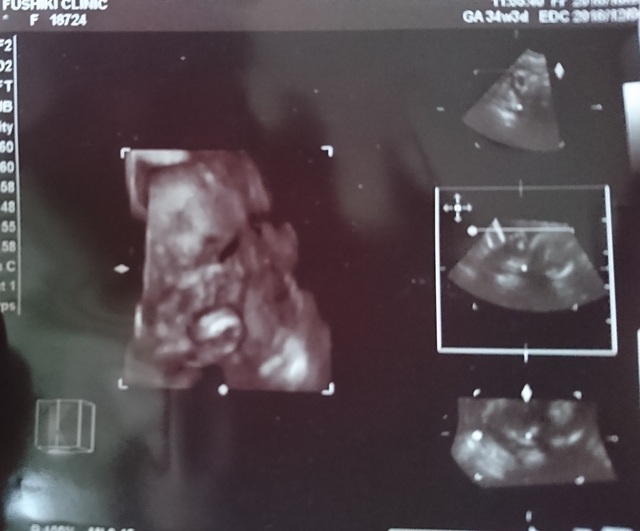

34週3日(32w3d・女の子)|らんらむ さん(24歳)

エコー写真撮影時のエピソード:

赤ちゃんの腕が顎に沿うようにV字になっていて、顔がニヤリと笑っているようで、決めポーズみたくて笑っちゃった1枚です。

この頃は体調も悪い所がなく、赤ちゃんも活発に動きすぎていて驚くくらい。産休にも入り心にも余裕が出来てとても調子が良かったです。